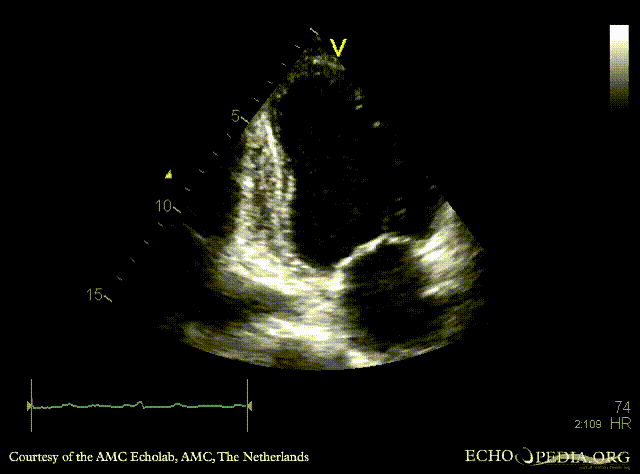

Case 95

Apical and anteroseptal infarction

A4CH: dilated left ventricle, poor function, akinesia of the apex and all midsegments A2CH